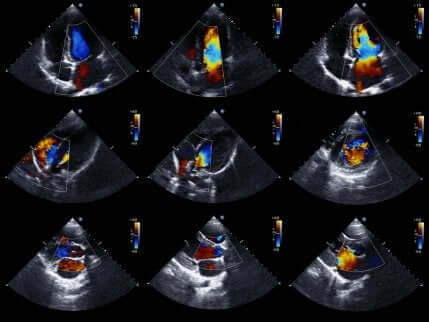

تخطيط صدى القلب

أخيرًا، يسمح تخطيط صدى القلب بدراسة نشاط القلب بمزيد من التفصيل. هذا الاختبار من الاختبارات الطبية الشائعة جدًا، وذلك لأنه يوفر صورًا متحركة للقلب.

عن طريق ذلك، يمكن تقييم حالة أجزاء القلب المختلفة وتحركاتها لتأكيد أو استبعاد الاحتشاء. بالإضافة إلى أنه يمكن من خلال هذا الاختبار تقييم حجم وقوة القلب.

وبشكل عام، هو اختبار غير غزوي ولا يعرض المريض لأي خطر لأنه يستعمل الموجات فوق الصوتية للحصول على الصور.

سيقوم الطبيب باستبعاد الاحتشاء في حالة وجود اضطرابات في جدران القلب. وإذا تم اكتشاف اضطرابات، يجب تقييم نتائج الاختبار مع الأعراض، فوجودها لا يقتصر على هذه الحالة فقط.